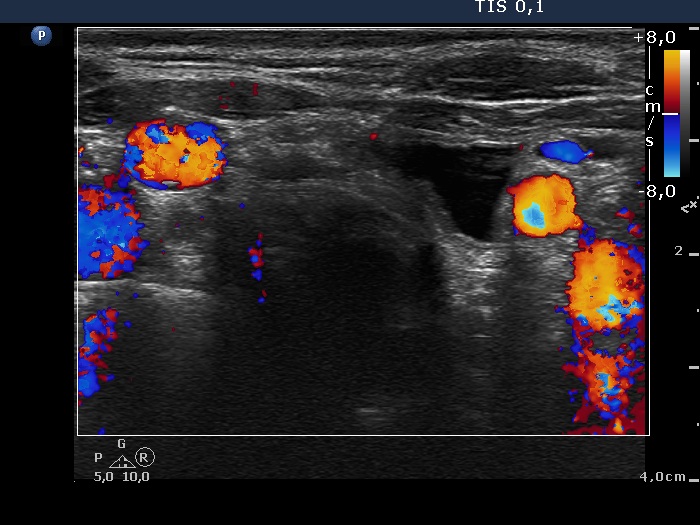

Parathyroid lesions - case cons100_028 (ultrasonographic picture 12)

Under the left thyroid lobe, transverse scan, color Doppler mode - after aspirating 16 mL watery fluid. A thin solid part can be seen in the dorsal part of the cyst.